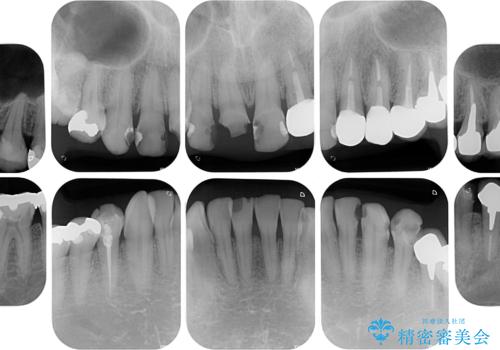

- すぐに欠けてしまう前歯や、むし歯で全顎的に処置された歯を気にして来院された患者様です。

元来むし歯が多く、さらに受け口傾向の咬み合わせを気にしていらっしゃいました。

当初はむし歯処置が必要な歯のみの治療予定でしたが、捻転や咬み合わせを可及的に改善したいとのことで、全顎的にオールセラミッククラウンにて補綴治療を行うこととしました。